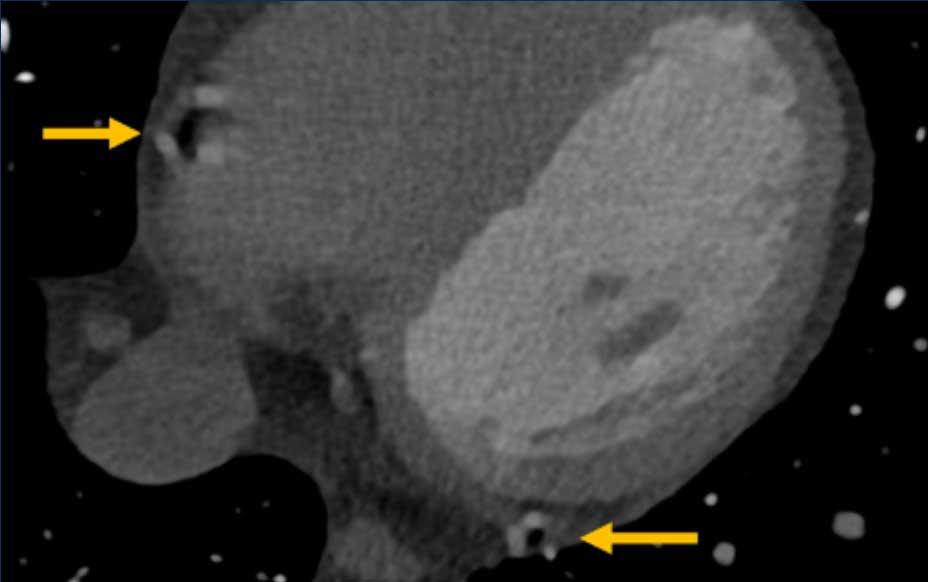

This image is of a patient with Kawasaki disease.

There is a coronary artery aneurysms (8 mm and 6 mm diameter)

of the LAD.

Please also note the presence of

partially calcified plaque in the proximal aneurysm.